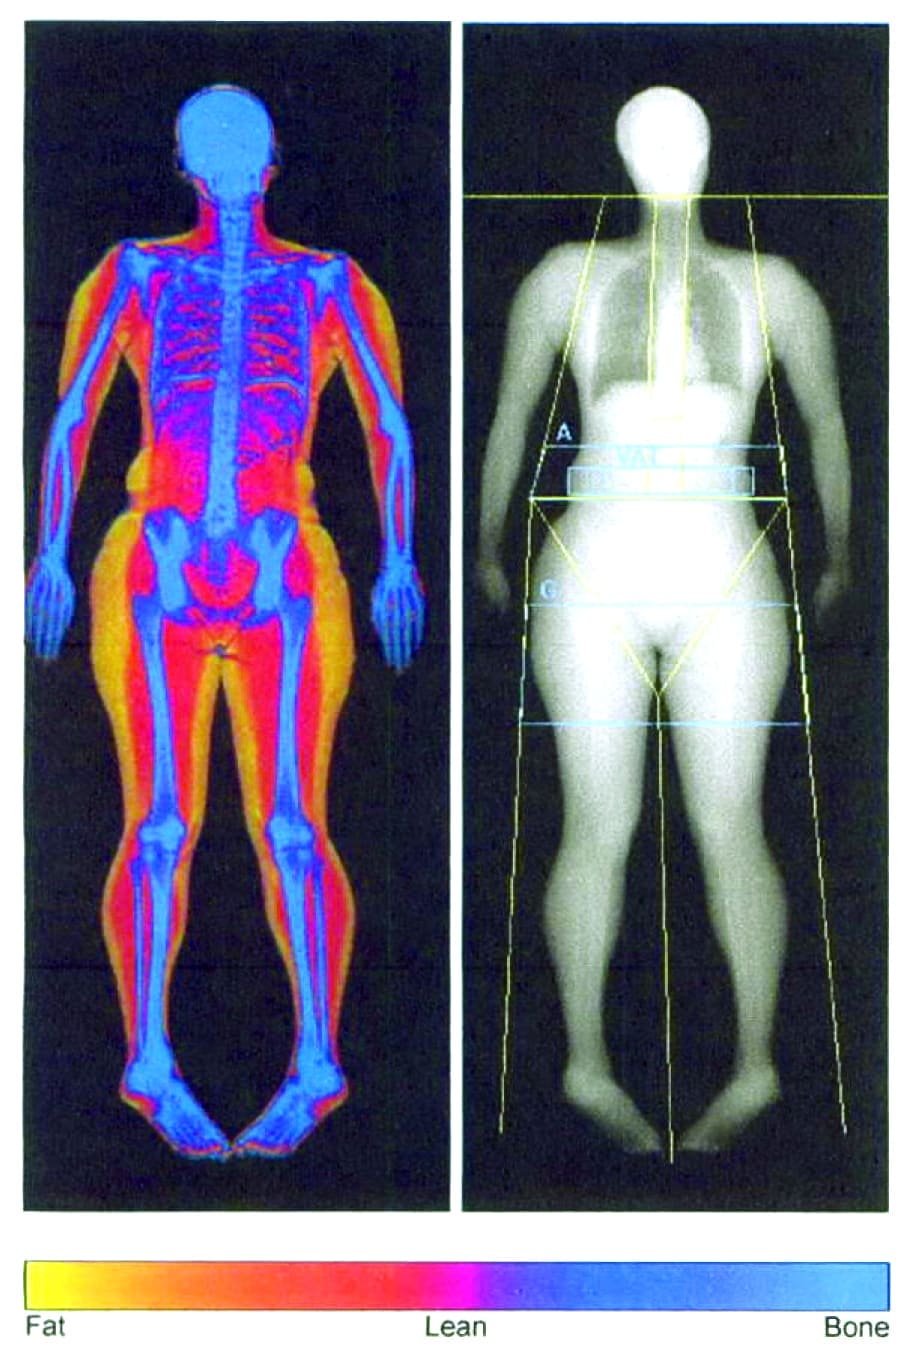

Diabetes Duo Center for Training » Body Composition Assessment and Analysis

Body Composition Analysis Real You Clinic Twickenham & Richmond

INBODY Scanning Body Composition Analysis

Give yourself the power of information body composition analysis at

Do you have questions about your InBody analysis? Tatyana's Fitness, LLC